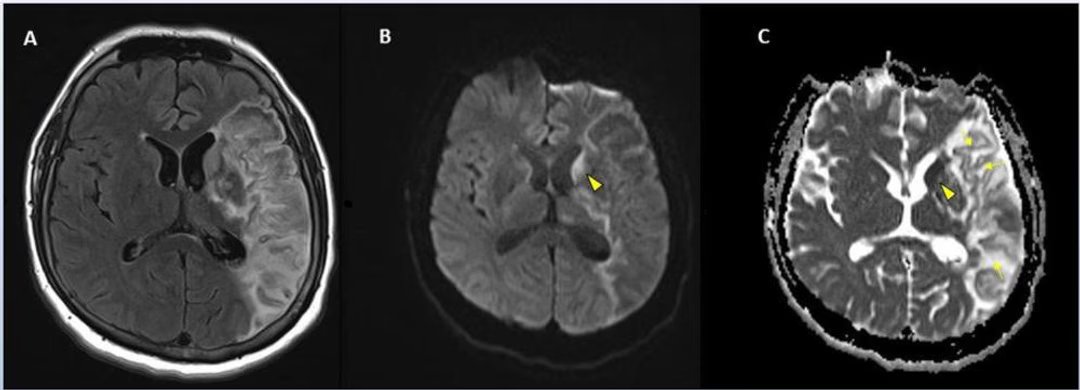

A evolução do tamanho das lesões cerebrais foi avaliada por ressonância magnética. ©RSNA

A eficácia de cada tratamento foi avaliada através de uma série de testes comportamentais, bem como pela análise de volume lesões cerebrais por ressonância magnética. Um método estatístico inovador foi aplicado para analisar dados em quatro etapas do processo de teste.